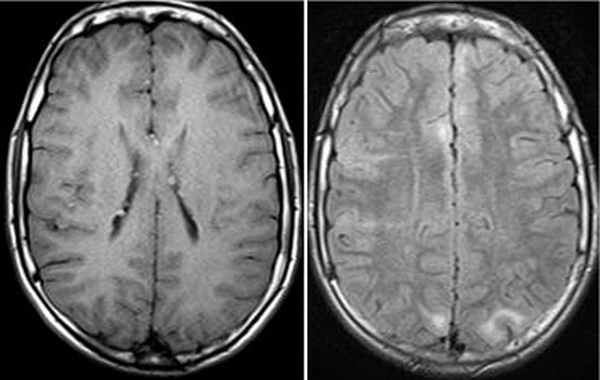

Субэпиндемальные узлы и корковые туберсы на МРТ

Наиболее типичными нарушениями в головном мозге являются корковые туберсы и субэпендимарные узлы. Туберсы могут быть как единичными, так и множественными, располагаются в виде выступов над единичной или прилегающими бороздами коры, расширяя их. Субэпендимарные узлы локализуются в стенках боковых желудочков и, реже, в стенках III и IV желудочков мозга. У новорожденных субэпендимарные узлы редко бывают кальцифицированными. По мере роста ребенка наблюдается постепенное отложение кальция в субэпендимарных узлах.

Субэпендимарные узлы в 10% случаев трансформируются в гиганто-клеточную астроцитому, которые манифестируют обычно между 5 и 10 годами жизни, имеют тенденцию к росту и локализуются у отверстия Монро